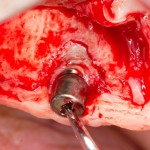

В-третьих, если вы уверены, что имплантат нужно удалить — сделайте это как можно раньше. Если развился периимплантит — ждать не имеет смысла. Имплант стопудово не интегрируется. А смысла ждать осложнений в виде потери костной ткани нет. В зависимости от локализации, отторжение имплантов нередко сопровождается потерей объемов костной ткани и слизистой оболочки. Если это происходит — проводится операция остеопластики и/или пластики мягких тканей. Лично мое мнение — пациент не должен дополнительно оплачивать работу, необходимость которой возникла из-за ошибки. Кто-то, правда, может считать иначе.

- удаление импланта — перерыв на 1-2 месяца (больше ждать не нужно, ибо атрофия костной ткани)

- реимплантация, иногда совместно с остеопластикой. Или остеопластика отдельным этапом (при необходимости).